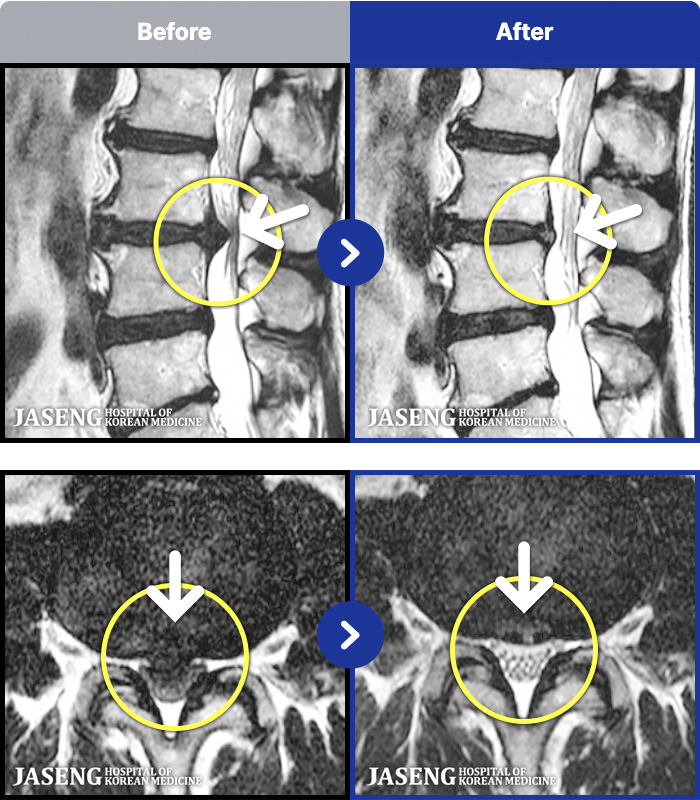

- MRI ġ

MRI ġ

1,237 MRI ũ ʸ Ȯϼ.